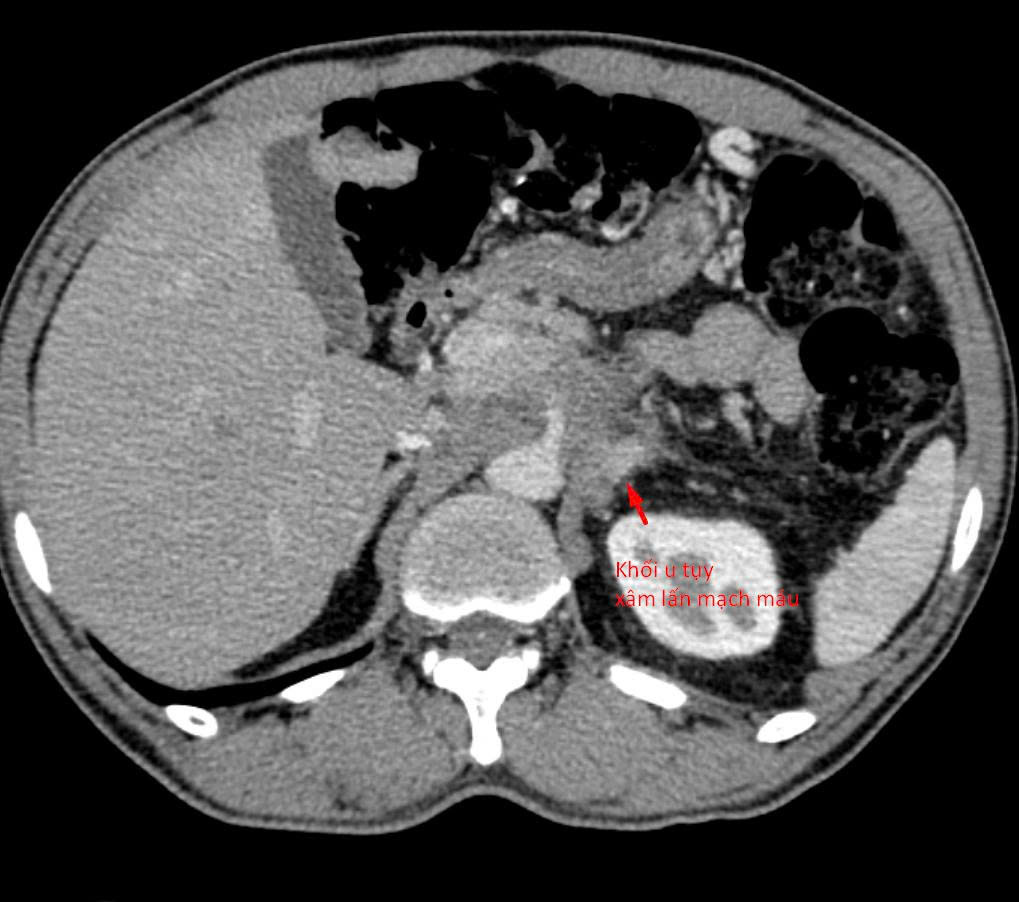

Bệnh nhân 64 tuổi (tại Hà Nội) có khối u tụy xâm lấn mạch máu được chẩn đoán tại nhiều bệnh viện khác nhau. Tuy nhiên, do khối u nằm ở vị trí đặc biệt phức tạp, áp sát nhiều cấu trúc nguy hiểm, các bác sĩ chưa thể tiến hành sinh thiết để xác định mô bệnh học – bước then chốt quyết định hướng điều trị ung thư.

Khối u tủy xâm lấn mạch máu.

Sau khi tiếp nhận bệnh nhân, các bác sĩ đã tiến hành đánh giá lại toàn bộ cấu trúc giải phẫu và đường tiếp cận khối u. Hầu hết các hướng sinh thiết thông thường đều không khả thi do nguy cơ tổn thương mạch máu lớn và các tạng quan trọng.